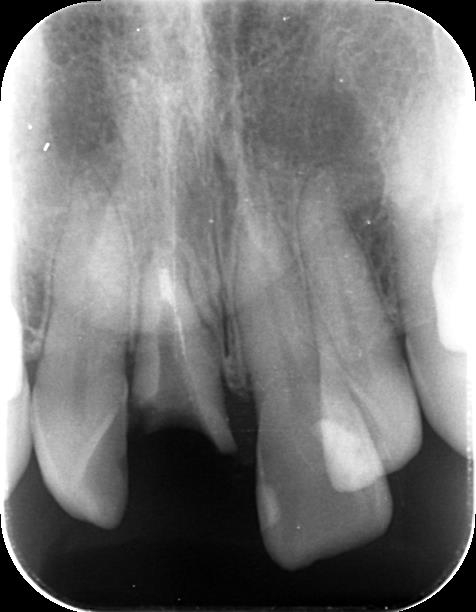

術前のデンタル写真

術前の予後不良の歯牙

術前の前歯は予後不良です。